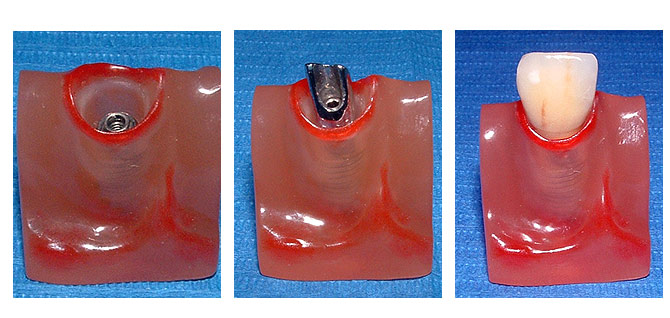

Einzelzahn

Das Implantat übernimmt die Funktion der eigenen Zahnwurzel. Ein ästhetisch ansprechendes Behandlungsergebnis ist hier besonders wichtig. Implantatgetragene, festsitzende Zähne sehen nicht nur aus wie eigene, sondern fühlen sich auch so an.